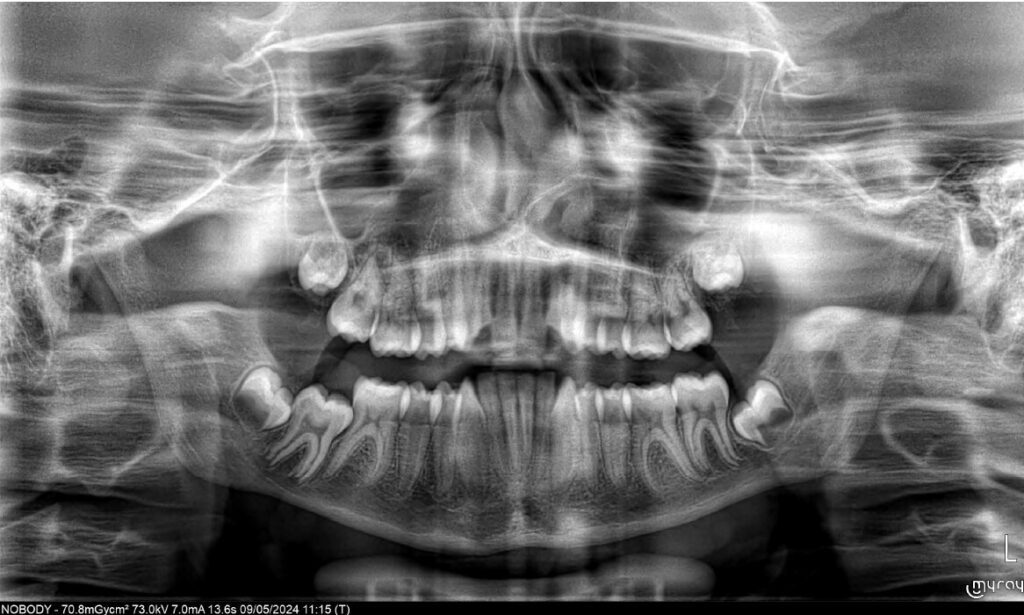

A 13-year-old male patient presented with a deep bite, characterized by near-complete coverage of the mandibular incisors. Clinical evaluation revealed bi-arch crowding, dental rotations, and proclination of the maxillary lateral incisors, contributing to the patient’s esthetic concerns. The facial profile was retrusive, consistent with mandibular retrognathism, and no significant periodontal abnormalities were detected.

The patient presented with a skeletal Class II relationship with bilateral molar and canine Class II and a Class II division 2 dental pattern. The deep bite was associated with anteroinferior crowding and an accentuated Curve of Spee. Facial analysis revealed good symmetry, a slightly increased lower facial third, and a convex profile characterized by mandibular and chin retrusion. Lip competence was mildly reduced, with a decreased nasolabial angle and mentalis hyperactivity, all of which compromised overall facial harmony.

- Initiation of mandibular advancement from the 4th aligner using mandibular advancement blocks;

- Selective interproximal reduction in the mandibular anterior region to create space and control incisor inclination;

- Intrusion of mandibular incisors and canines to level the Curve of Spee;